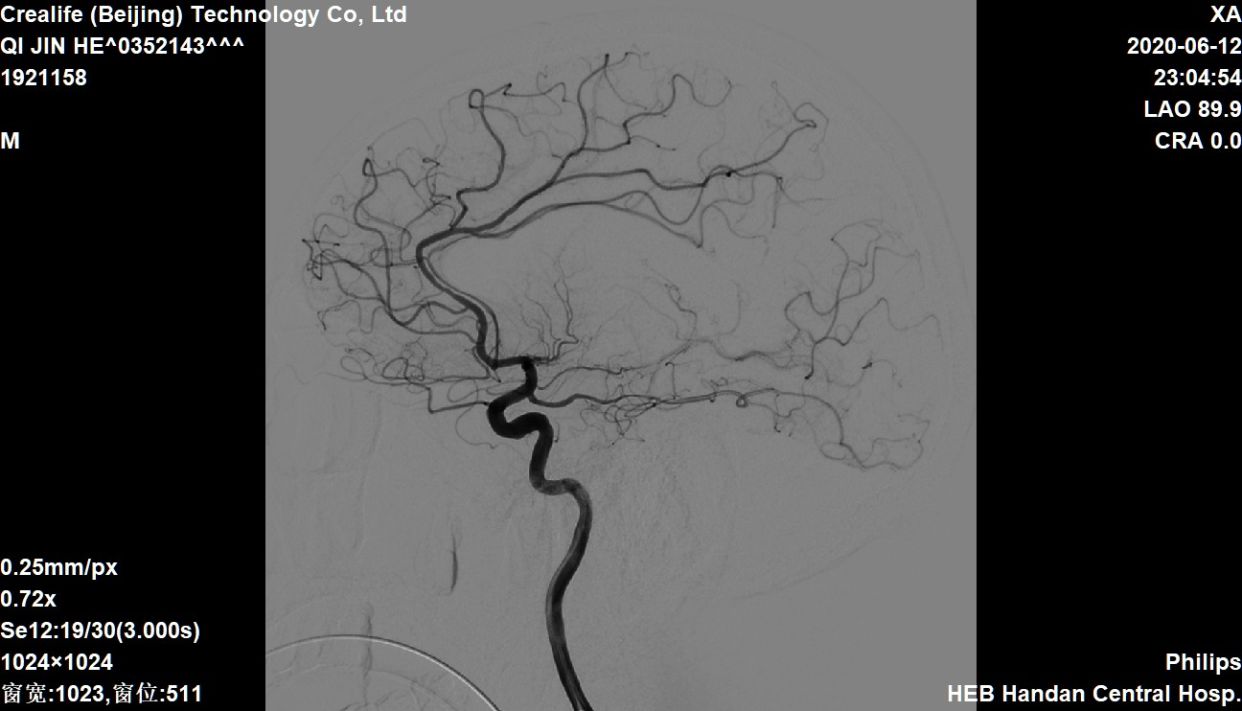

侧位

椎动脉造影,左侧软膜支有少量代偿

右侧大脑中动脉向左侧未见代偿

急性左侧大脑中动脉闭塞,考虑栓塞